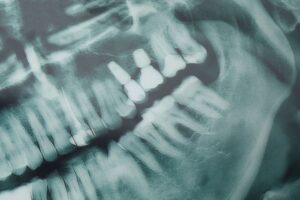

Osseointegration is the process by which a dental implant, made from biocompatible materials, bonds directly with the bone in your jaw. Unlike other tooth replacement options that simply sit on the gumline, like dentures, implants become part of your body’s bone structure. This offers a level of stability and durability that functions just like your natural teeth.

The bonding process happens at a cellular level. Once the implant is placed in your jawbone, the bone cells begin to attach themselves to the surface of the implant. They gradually grow around the metal implant “root.” Over time, this creates a solid anchor for the implant crown or bridge to be placed on top.

Dental implants are commonly made from titanium. Titanium is a biocompatible metal, meaning it’s highly unlikely to cause a negative reaction in the body. This allows bone cells to safely interact with the surface of the implant without being rejected. Additionally, titanium is strong, lightweight and corrosion-resistant, making it ideal for long-term use in the body.

The surface of the titanium implant is often treated to make it more porous, which encourages bone cells to grow into these tiny spaces, further enhancing the bond between the implant and the jawbone.